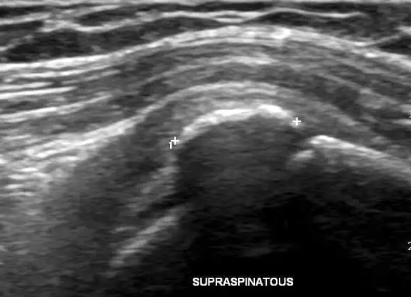

필요에 따라 초음파, MRI로 동반 손상을 확인하기도 합니다.